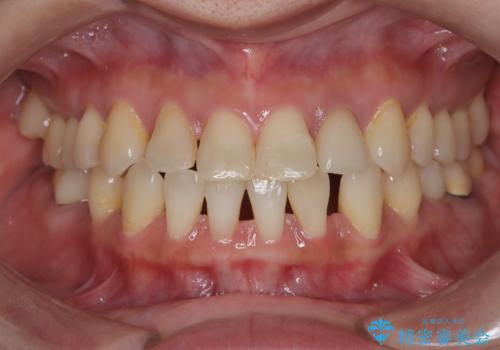

前歯の突出と下顎の偏位を改善。審美ワイヤーで整えるバランスの良い歯並び